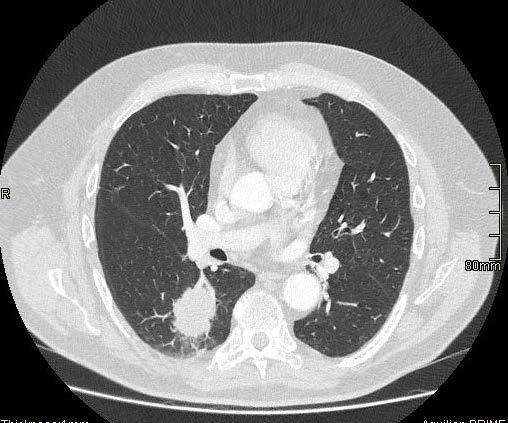

Mynd 6-1 Lítið lungnakrabbamein í hægra lunga (ör) sem fannst við skimun með tölvusneiðmyndum.

Með tilkomu tölvusneiðmyndatækni (TS) varð unnt að finna mun smærri hnúta í lungum en áður var mögulegt með hefðbundnum röntgenmyndum (mynd 6-1). Á síðustu áratugum hefur verið efnt til stórra framvirkra samstarfsverkefna, bæði í Bandaríkjunum og Evrópu. Fyrstu rannsóknir á skimun með TS voru gerðar í Japan og fyrsta alþjóðlega rannsóknin benti til þess að unnt væri að finna um